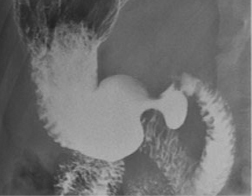

| TOGD de estomac normale en

double de contrast |

Ulcere de la petite courbure en double de

contrast |

Images en double de contrast

d'une ulcere du paroi posterieure de estomac . |